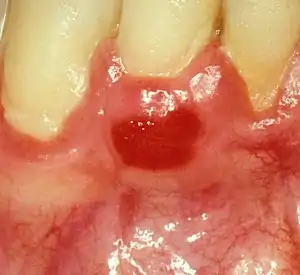

| Plasma cell gingivitis in an adult (histologically verified). |

Plasma cell gingivitis appears as mild gingival enlargement and may extend from the free marginal gingiva on to the attached gingiva.[6] Sometimes it is blended with a marginal, plaque induced gingivitis, or it does not involve the free marginal gingiva. It may also be found as a solitude red area within the attached gingiva (pictures). In some cases the healing of a plaque-induced gingivitis or a periodontitis resolves a plasma cell gingivitis situated a few mm from the earlier plaque-infected marginal gingiva. In case of one or few solitary areas of plasma cell gingivitis, no symptoms are reported from the patient. Most often solitary entities are therefore found by the dentist.[2]

The gums are red, friable, or sometimes granular, and sometimes bleed easily if traumatised.[6] The normal stippling is lost.[7] There is not usually any loss of periodontal attachment.[6] In a few cases a sore mouth can develop, and if so pain is sometimes made worse by toothpastes, or hot or spicy food.[7] The lesions can extend to involve the palate.[7]